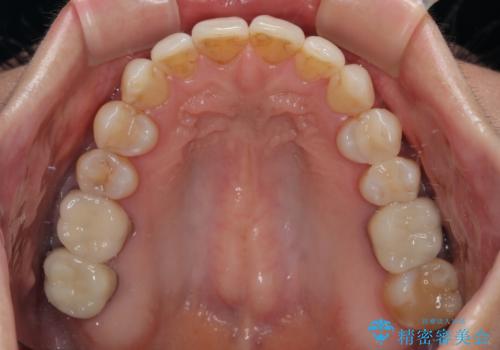

- 上下前歯のデコボコと、奥歯の銀歯を気にして来院された患者様です。

概ね歯列が整ったところで銀歯の全てをセラミッククラウンなどに置き換え、その後インビザラインを1セット使用して仕上げていくこととしました。

矯正治療の後半にはホワイトニングもされ、スッキリした口元に仕上げることができました。